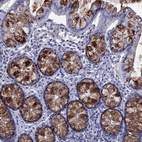

Immunohistochemistry analysis in human colon and skeletal muscle tissues using HPA035464 antibody. Corresponding TFF3 RNA-seq data are presented for the same tissues.